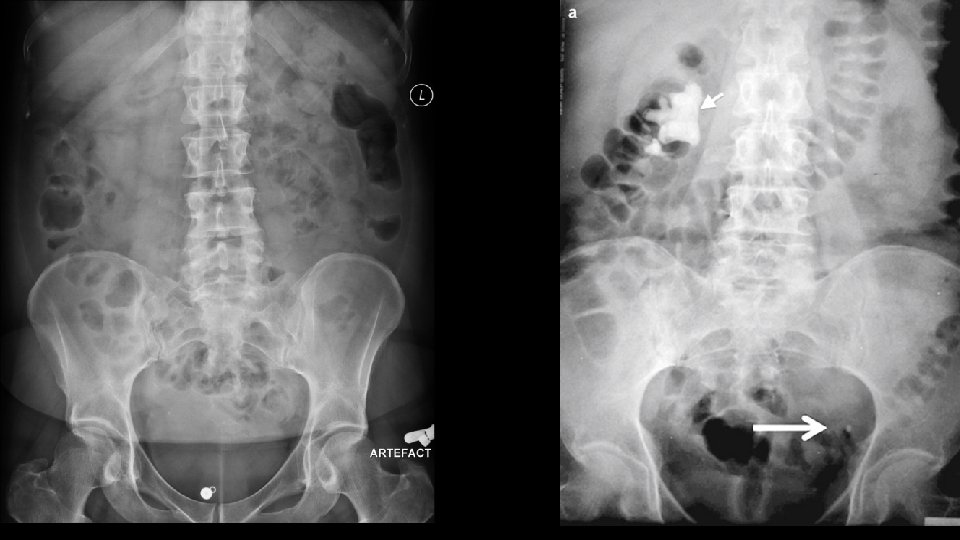

ABC of abdominal radiographs • A for Air • B for Bowel • C for Calcification

C for calcifications • Calculi – here, there and everywhere • Organ calcifications

Urolithiasis Calculi along urinary tract • Anywhere • Kidney • Ureter • Bladder